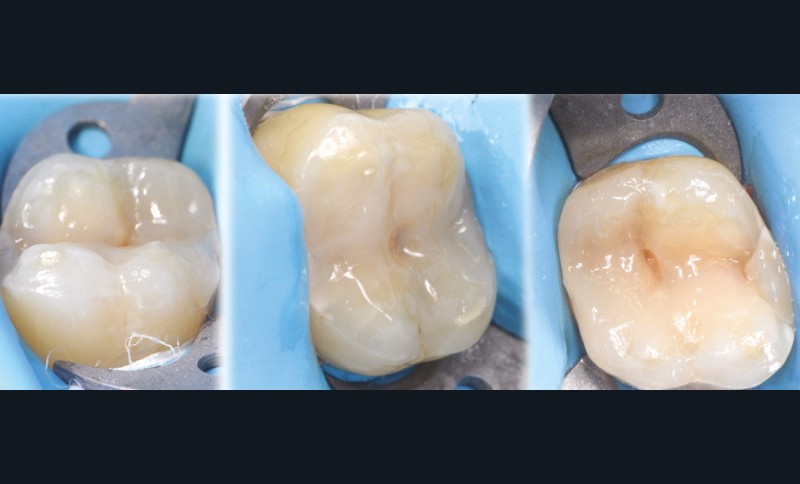

Les overlays (céramique et composite) sont devenus en quelques années un véritable référentiel en termes de restaurations partielles postérieures. Ils sont même les successeurs contemporains de la couronne périphérique dans bon nombre de situations, que ce soit sur dent pulpée présentant un délabrement coronaire important ou sur dent dépulpée pour laquelle le recours au recouvrement de la totalité de la face occlusale est souvent jugé plus indiqué (fig. 1 à 4).

à ces restaurations correspond aujourd’hui toute une série de nouveaux design postérieurs permettant une ultra-préservation tissulaire et pouvant s’inscrire, en fonction des situations cliniques, dans l’émail (situation idéale), dans la dentine, dans le composite de base intermédiaire, ou un « mix » de ces différents supports (fig. 10 à 13).